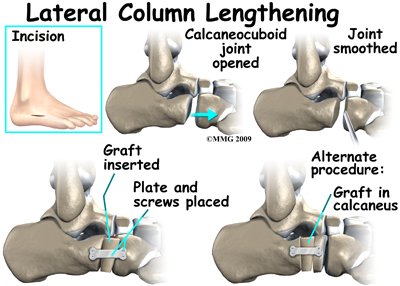

The most common surgical procedures used with this condition include arthrodesis (fusion), osteotomy (cutting out a wedge-shaped piece of bone), and lateral column lengthening. Lateral column lengthening involves the use of a bone graft at the calcaneocuboid joint, which helps restore the medial longitudinal arch (arch along the inside of the foot).

It's not clear yet from research evidence which surgical procedure works best for this condition. A combination of surgical treatments may be needed. It may depend on your age, type and severity of deformity and symptoms, and your desired level of daily activity. Studies do show, however, that long-term results of just reconstructing the posterior tibial tendon have been disappointing. As much as a 50 per cent failure rate has been reported which is likely because of the complexity of soft tissue interactions needed to maintain structural integrity of the foot. Reconstructing the spring ligament complex or using an osteotomy to lengthen the lateral side of the foot along with a tendon transplant is more likely to restore more normal foot and ankle movement with better results.